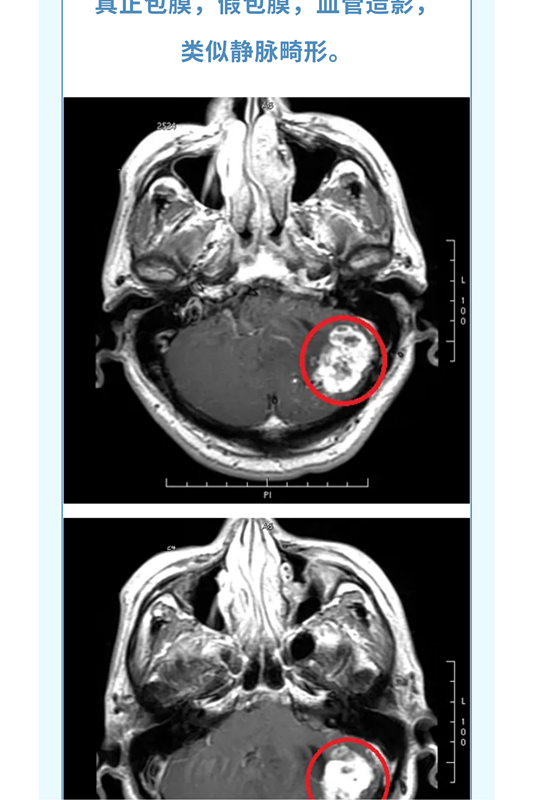

神经导航辅助下改良枕下天幕上入路治疗复杂小脑山坡实质性血管母细胞瘤

血管母细胞瘤( 血管网状细胞瘤、血管网织细胞瘤):为良性肿瘤, 有人认为其起源于血管周围的间叶细胞, 好发小脑中线旁,占颅内肿瘤的1%,后颅窝肿瘤的7%; 主要发生于成人(30~40岁多见);儿童期和老年人少见,男性较女性多见; 分为散发性和家族遗传性两种,后者表现为VHL病。多发者高度提示VHL病。